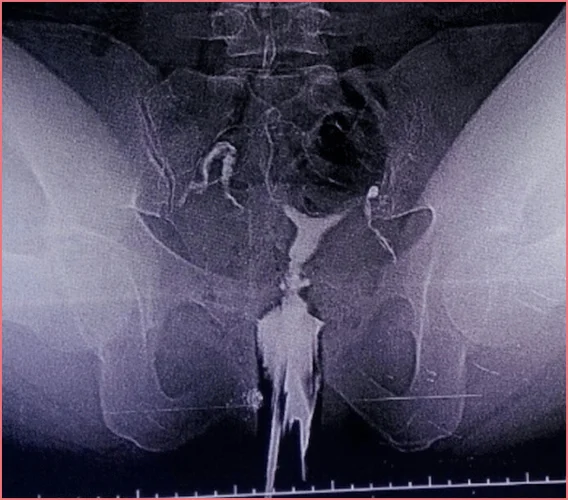

Rahim içinin ve tüplerin kontrast madde verilerek radyografik yöntemlerle incelenmesine HSG (histerosalfingografi) yani Rahim Filmi denir. HSG 50 yıldan uzun süredir uygulanan bir tanı yöntemidir. İşlem esnasında kullanılan sıvı herhangi bir sıvı değil, röntgen cihazları tarafından görülebilen radyoopak- kontrast dediğimiz türden bir sıvıdır. Rahim içi ve tüpleri uygun hızla ve basınçla doldurabilmesi için özel bir kıvama da sahiptir. Normal uterus ve tubalara sahip kadında, opak madde rahim ağzından hafif basınçla rahim içine verildikten sonra rahim içini ve tüpleri zorlanmadan geçer ve bu alanları röntgen filminde görünür hale getirir. Skopi dediğimiz röntgen bulgularını anında görmemizi sağlayan cihaz sayesinde bu geçiş aşamalarını tek tek gözlemleyebiliriz ve işlemin başarısız olma ya da tekrarlanma olasılığını azaltmış oluruz.

HSG sayesinde rahim içine bebeğin yerleşmesine engel olan miyom, polip gibi kitleleri görebiliriz. Yine daha önce geçirilmiş kürtaj ya da biyopsi gibi rahim içi cerrahi işlemler sonrası ya da ağır bir pelvik enfeksiyon neticesi gelişebilen yapışıkları belirleyebiliriz. Doğuştan mevcut olan rahim şekil bozukları (uterus bikornis-çift rahim, unikorn rahim ya da septum gibi) da Rahim Filmi ile tespit edilebilir.

Tüplerde sperm ile yumurtanın birleşmesini engelleyecek bir tıkanıklık ya da spermin yumurtaya doğru ilerlemesini engelleyecek balonlaşmalar da yine HSG ile rahatlıkla tespit edilebilir. Rahim Filmi sonrası çekilen kontrol filminde opak maddenin karın içinde dağılım şekline bakarak rahim etrafındaki dokularda bulunan yapışıklıklar ve düzensizlikler tespit edilebilir.